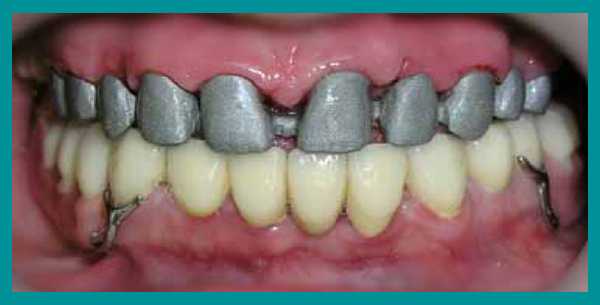

Осмотр выявил очень сильную горизонтальную стираемость верхних и нижних зубов, снижение высоты прикуса и изменение его из нормального в обратный (нижние зубы при смыкании находились впереди верхних). Одновременно на ортопантомограмме височно-нижнечелюстного сустава определялся двухсторонний подвывих нижней челюсти.

1 этап лечения

Сначала были изготовлены на верхнюю и нижнюю челюсти два пластинчатых протеза с небольшим повышением прикуса. Появилось равномерное смыкание задних зубов, результатом чего стала возможность пережевывания пищи.

4 этап лечения

После появления необходимой высоты прикуса на передние зубы были изготовлены и установлены пластмассовые корневые вкладки и на них выполнены временные коронки.

Изготовление металлических вкладок пока было преждевременно, так как можно было ошибиться с размером и наклоном в переднезаднем направлении. С появлением временных пластмассовых коронок пациент стал улыбаться, смог не только пережевывать, но и откусывать пищу передними зубами. Так как изменение высоты прикуса происходило постепенно, пациент быстро и благополучно привыкал к создавшемуся положению и явлений дискомфорта не испытывал.

5 этап лечения

Когда необходимая высота прикуса была достигнута, были изготовлены металлические корневые вкладки. Далее были созданы бюгельные протезы на кламмерах с использованием металлокерамических коронок в виде опорных зубов.

После фиксации металлокерамических коронок на постоянный цемент, коррекции и установки бюгельных протезов на кламмерах, пациент получил рекомендации по уходу за зубными протезами и проведению личной гигиены полости рта. План лечения был выполнен. Рекомендовано профилактическое посещение стоматолога каждые четыре месяца.